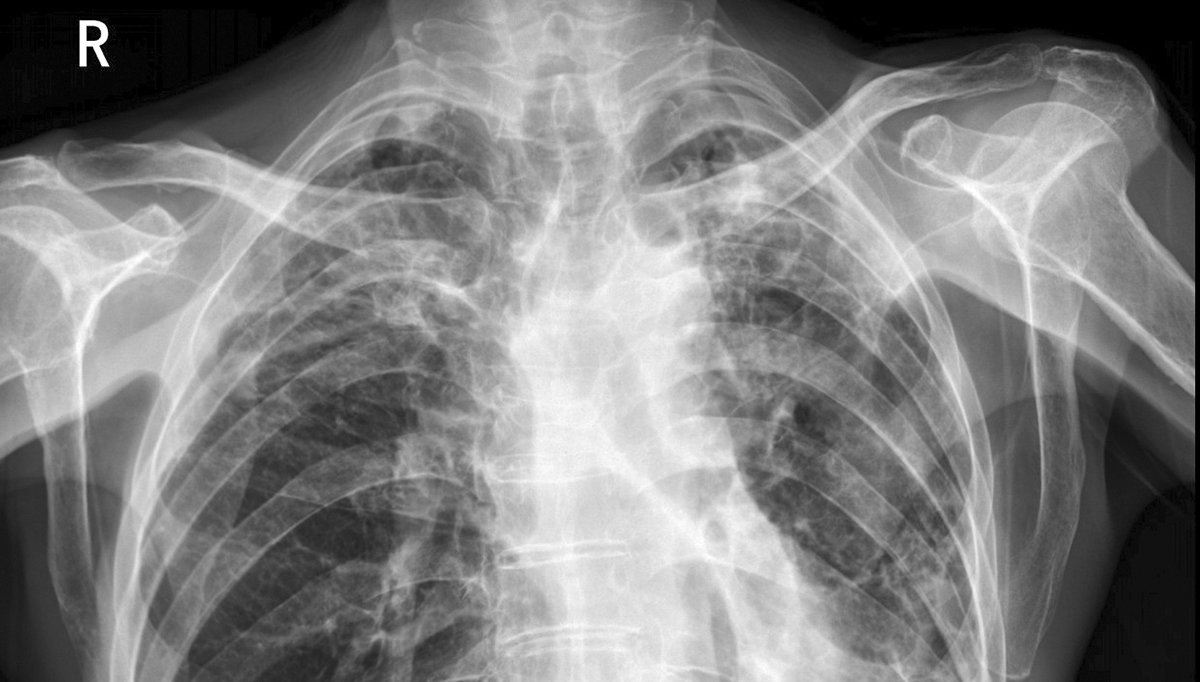

其次是诊断精度的显著提升。人工阅片受视觉疲劳、经验差异影响,对5m 以下的肺微小结节、乳腺微钙化等细微病灶漏诊率达22%,而医疗影像诊断软件通过3D卷积神经网络等技术,对磨玻璃结节的检出敏感度达98.7%,能精准标记病灶位置与特征,降低漏诊率,同时提升不同医生间诊断结果的一致性。